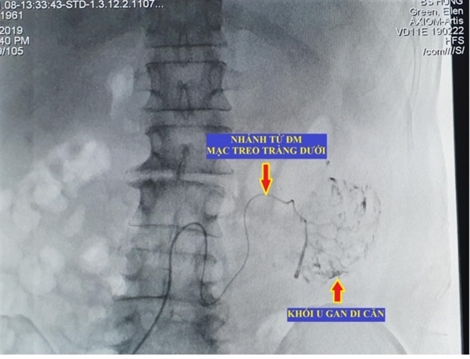

Bác sĩ cảnh báo ung thư gan từ u gan lành tính

Bệnh nhân 34 tuổi bị u máu trong gan lành tính chuyển thành ung thư gan di căn vừa được phát hiện tại BV Hữu nghị Việt Đức là một trường hợp đáng tiếc. Đây là chia sẻ của TS.BS Đỗ Tuấn Anh, Trưởng Khoa Phẫu thuật Gan mật, BV Hữu nghị Việt Đức tại chương trình khám miễn phí về bệnh lý u gan diễn ra ngày 25/7.